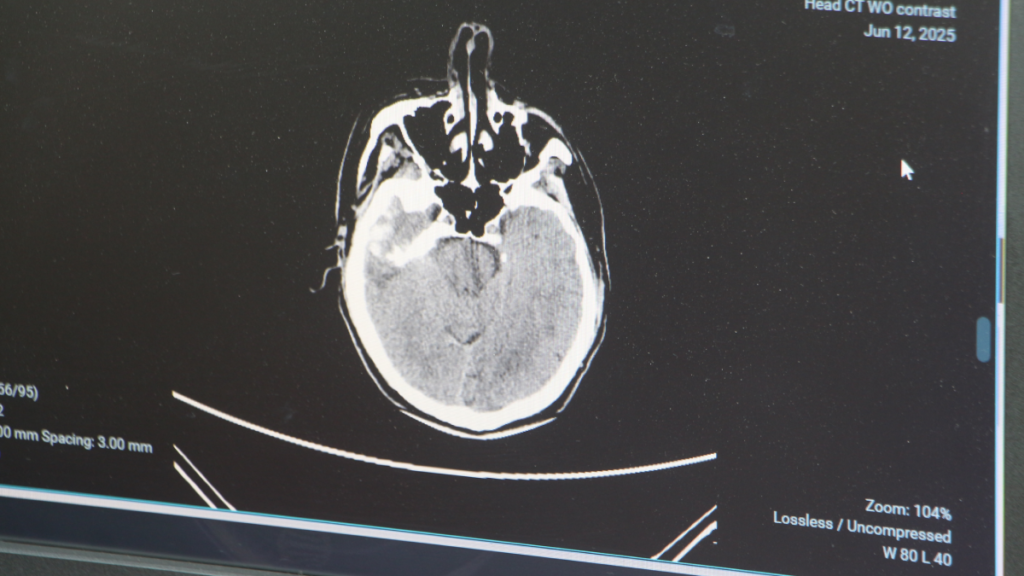

Gençlerde beyin kanaması görülme oranı giderek artıyor

Son yıllarda 50 yaş üstünde görülen beyin kanamaları, gençlerde de artış gösteriyor. Adana Şehir Hastanesi Beyin ve Sinir Cerrahisi Bölümü'nden Doç. Dr. Ali İhsan Ökten, bu durumun başlıca nedenlerinin 'arteriyovenöz malformasyon' ve 'anevrizma' olduğunu belirtiyor. Anevrizma, yani damar duvarlarındaki baloncuklar nedeniyle oluşan beyin kanamalarının 100 binde 10-15 kişide görüldüğünü, ancak gençlerde bu oranın yükseldiğini vurguluyor.